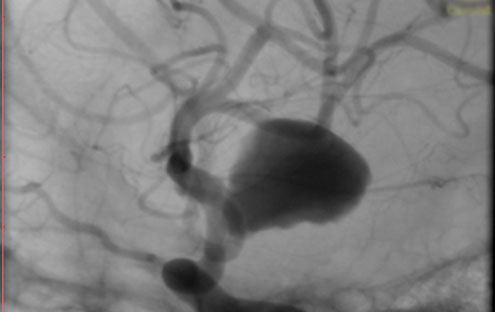

La paciente ingreso al Servicio de Hemodinamia el día martes 11 de febrero con un aneurisma cerebral gigante en la carótida izquierda y se le practicó una embolización; es decir una oclusión por dentro del mismo, donde se colocó un dispositivo denominado coils más un stent diversor de flujo. El procedimiento fue exitoso y contó con la colaboración de médicos neurointervencionistas del Instituto Oulton de la Ciudad de Córdoba.

La paciente llevaba un tiempo refiriendo dolores de cabeza, trastornos visuales por lo cual luego de realizarcele los estudios pertinentes y comprobar la patología se programó el procedimiento. Debido a que el Hospital Vera Barros no contaba con la tecnología necesaria para esta práctica compleja es que se realizó en la nueva Sala de Hemodinamia de INCOR en el marco de un convenio de trabajo conjunto entre la salud pública y la privada.